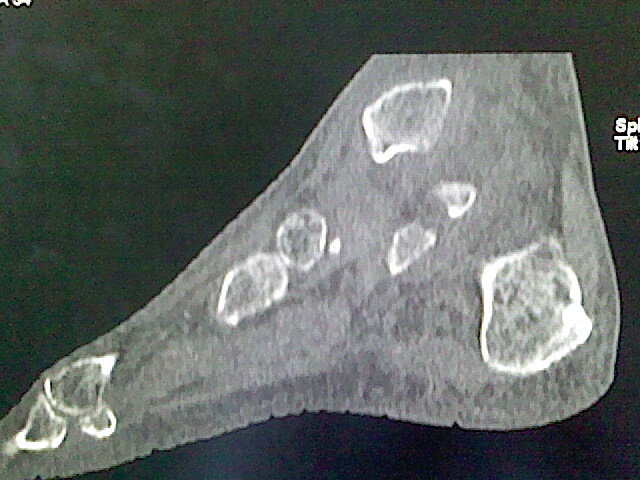

标题: CT16814:男,76岁,左小腿疼痛,不能站立 大家给看看 [打印本页]

男,76岁,左小腿疼痛,不能站立

本例骨质改变主要表现为滑膜或韧带区的骨侵蚀融解(胫腓联合区骨质破坏无硬化边),距骨后部骨质破坏区有硬化边及死骨样改变.所以,本例考虑关节结核可能性大,绒毛膜结节性滑膜炎多发于中年,且极少见于膝髋以外的关节,骨质硬坏也以压陷吸收为主,有明显的硬化边,骨膜增生呈结节状(可以mr鉴别),所以本例暂除外.

另不除外可引起相似表现的其他炎症如布氏杆菌性关节炎等